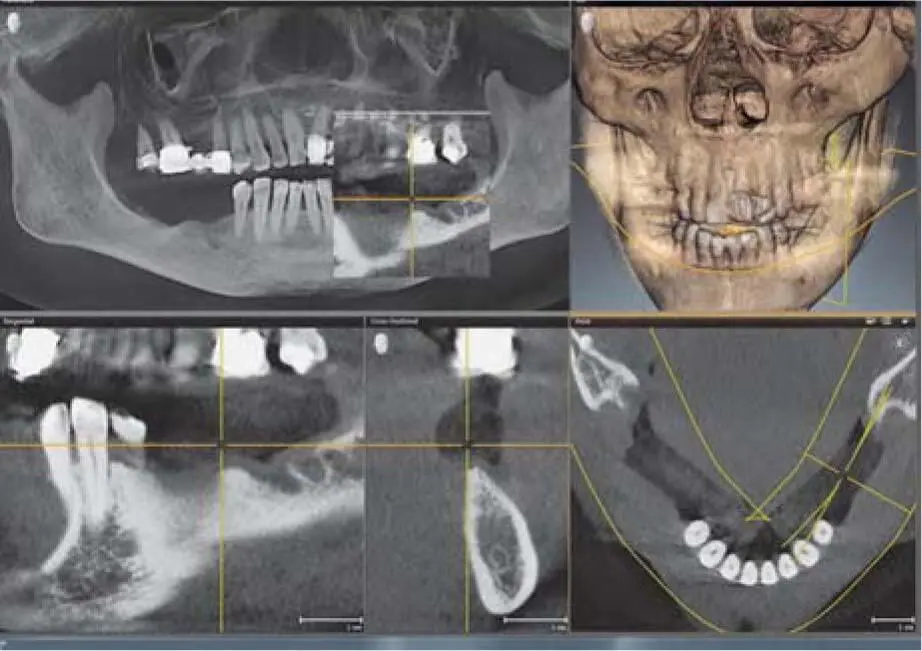

In addition to the reconstructions in the classical radiologic layers, special dental CT reconstructions are also possible, which offer sections perpendicular to a panoramic curve ( Fig 2-17cto h). For dental diagnostics, the images are exported in DICOM format so that they can be read in the various viewing and planning software. 1In addition to a precise representation of the bony structures, the spiral CT is particularly distinguished in the imaging of soft tissue ( Fig 2-18ato e). Although radiation exposure has been reduced in modern devices, the spiral CT still presents a higher radiation exposure compared with digital volume tomography devices (CBCT). 56

Fig 217cCT images of the mandible in the context of augmentation planning the - фото 80

Fig 2-17cCT images of the mandible in the context of augmentation planning: the layers are 1 mm in thickness.

Fig 217dCT images of the maxilla with the same thickness Fig 217eMultiple - фото 81

Fig 2-17dCT images of the maxilla with the same thickness.

Fig 217eMultiple slices from the posterior region of the mandible Fig - фото 82

Fig 2-17eMultiple slices from the posterior region of the mandible.